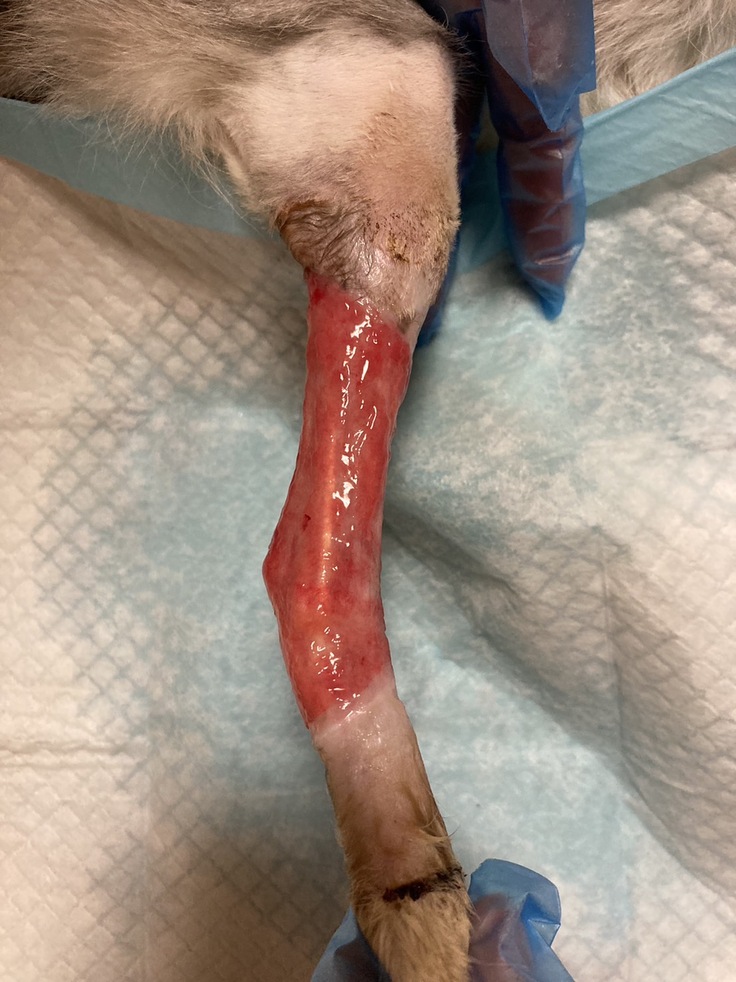

病院にて怪我の状態を確認したところ傷口の中からキツく巻きつけられ組織に食い込んだ紐のようなものが出てきました。

※皮下組織に食い込んでいた物、除去の際に壊死した組織も一緒に除去しました。

虐待により足を縛られどのくらいの期間を過ごしていたのかはわかりませんがハッピーの足は大腿部から足首までの皮膚がただれ、皮もめくれ、壊死した部分もかなりありました。

それから9ヶ月間、通院と一日2回の包帯交換を続けてまいりましたが経過は一進一退で芳しくなく皮膚の再生はほんの僅か、いつの日か完治することだけを願うばかりでした。

※皮膚再生治療中の患部

そんな中とうとう恐れていた感染症にかかり傷口の状態が悪化、4件の病院をまわりましたがどの病院にも切断を勧められ、切断の選択肢しかないのかと藁にもすがる思いで外科専門病院へ行き相談いたしました。

先生の判断では、まずは感染症を薬で抑えこのまま再生治療を続けましょうとのことでしたが、その頃のハッピーは怪我の足を一切使わない生活を送っておりその旨をお伝えしたところ、切断も視野に入れて治療を続けますが一旦投薬にて炎症を抑え経過が良好であれば皮膚移植をお勧めします、とのことでした。